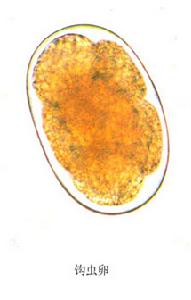

鉤蟲卵是鉤蟲的卵。鉤蟲卵屬蟲卵,是卵殼薄,無色透明。

名詞 簡介。若患者便秘或糞便放置過久,卵內細胞可繼續分裂為多細胞期。十二指腸鉤蟲卵與美洲鉤蟲卵極為相似,不易區別生活史 十二指腸鉤蟲與美洲鉤蟲的生活史基本...、腹痛、噁心、腹瀉、貧血鉤蟲(hookworm)是鉤口科線蟲的統稱,發達...